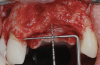

To enhance the esthetic outcome of the implant therapy, a split-thickness flap was opened at the level of the occlusal and buccal aspects of the implants. Two connective tissue grafts (CTGs) were harvested from the palate and sutured over the implants (Figure 11). Two additional CTGs were also obtained and positioned between the implants to augment the peri-implant papillae. This augmentation technique has been described as the "iceberg" connective tissue graft (iCTG) approach (Figure 12).16 The flap was released and sutured to completely cover the CTGs.

Fig 11. Soft-tissue augmentation with two CTGs.

Figure 11

Fig 12. Two additional CTGs were placed between the implants (ie, the “iceberg” CTG approach).

Figure 12